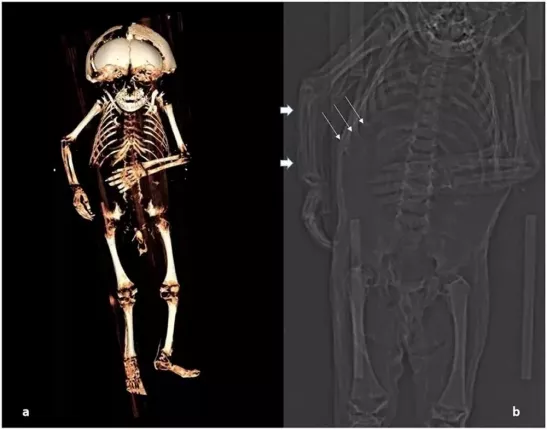

Frontiers in Medicine'de yayımlanan çalışmada araştırmacılar, bulguların tarihi Avusturya aristokrat toplumuna ender bir bakış açısı sağlayabileceğini söyledi. CT taraması kullanan bilim insanları, mahzen koşullarında doğal yollarla mumyalanan 'mumya bebek' üzerinde 'sanal otopsi' yaptılar. Bebeğin erkek olduğu, yaşına göre fazla kilolu olduğu anlaşıldı. Ölüm tarihinin ise MS 1550 ile 1635 arasında olduğu ortaya çıktı.

Bilim insanları, diş patlamasını, vücudunun kemiklerinin oluşumunu, uzunluğunu inceleyerek, çocuğun yaklaşık 1 yaşında olduğunu tahmin edebildiler. Kemik incelemesinde, bozuk kaburgalarında raşitik tespih belirtileri bulan araştırmacılar, D ve C vitamini eksikliklerinden kaynaklı hastalık olduğunu belirttiler.